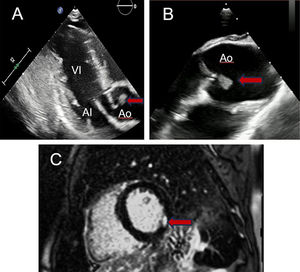

- IAMSEST en paciente de 16 años con colitis ulcerosa

- Diana Ladera Santos, Álvaro Roldán Guerra, Manuel Anguita-Sánchez

- Rev Esp Cardiol. 2024;77:971-2